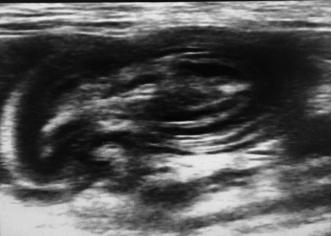

d.超声检查。消化道超声部分属于其他范畴,此处不做赘述。能够识别肠套叠即可。

犬猫呕吐的鉴别诊断,犬猫呕吐的诊断和治疗

肠套叠,可见肠道内容物有肠道分层结构